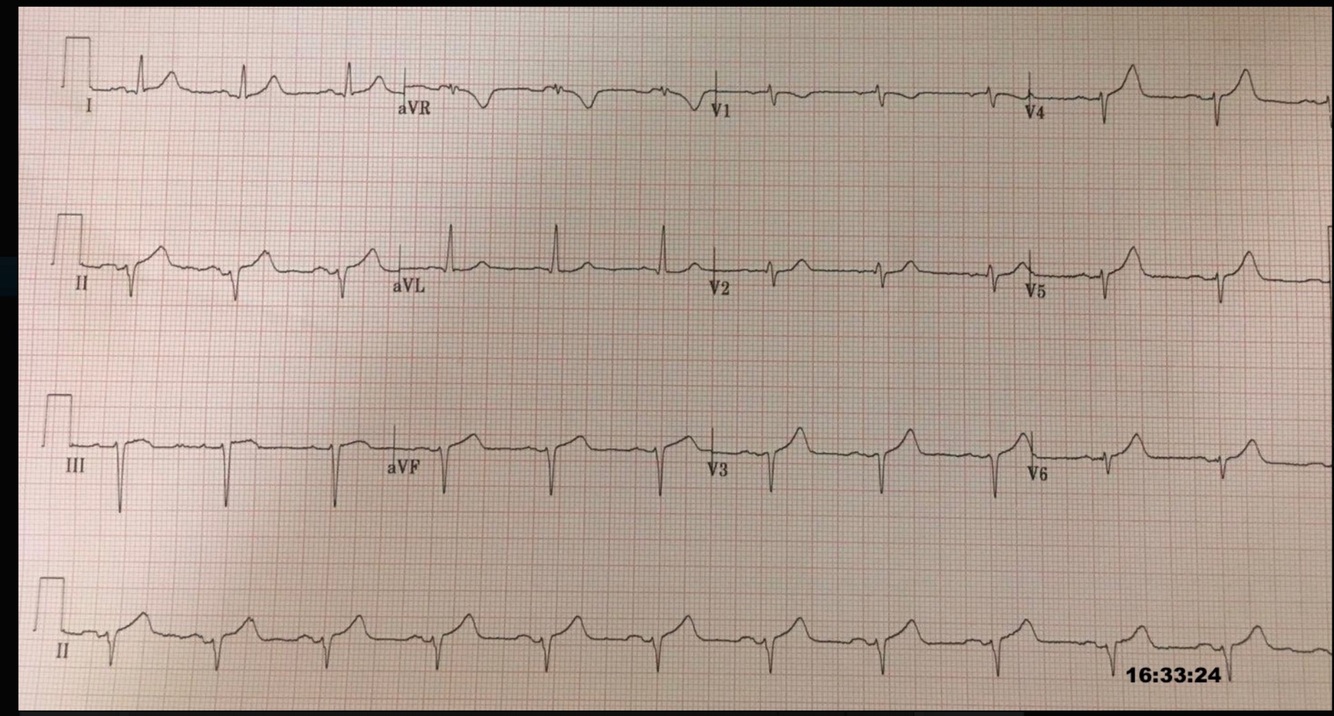

Hyperacute T-waves - Inferior 3

Broad, asymmetrically peaked or ‘hyperacute’ T-waves seen in early stages of MI.

Disproportionately increased area under the ST segment and T wave compared to the QRS

“Inflating the T-wave like a balloon”

De Winter pattern = tall, prominent, symmetric, anterior precordial T waves with upsloping ST segment depression